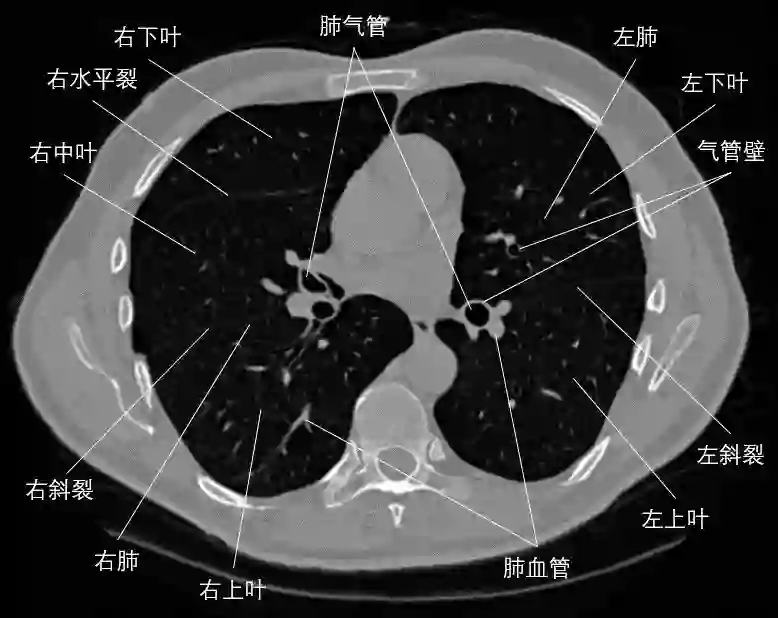

图1  一层肺部CT横断面图像结构示意图

本文通过对相关领域有代表性或前沿性文献的归纳总结,系统性地梳理了现有肺组织、肺气管、肺血管、肺裂纹、肺叶或肺段等解剖结构CT图像分割方法的主要流程、方法理论、关键技术和优缺点,讨论了各解剖结构分割的参考数据获取、实验设计方法和结果评价指标。